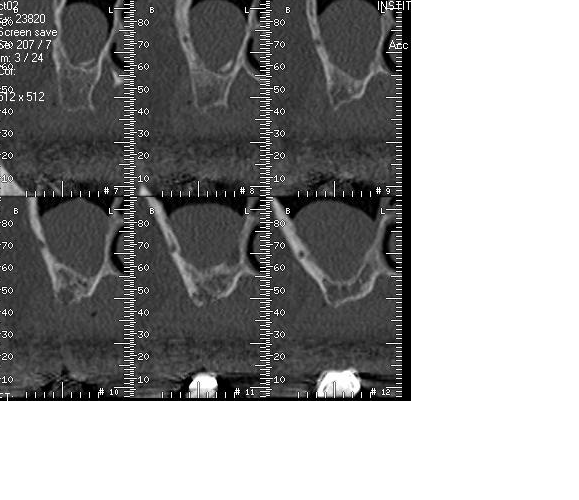

les scans donc.; sur la coupe 7 et 8 haut droite on voit un residu de je sais trop quoi, vraisemblablement l yperplasie est est due à cela..

Radiographiquement ca ressemble à un polype mais ce qui me gene c'est le residu qu'on voit dans le sinus. Si c'est la cause de l'inflammation, envoie ton patient chez l'ORL...c'est plus sure. tu as egalement de sacrés septa ton decollement ne sera pas evident.

ah ok!! mais les ballonnets sont plus un gadget commercial, g un confrere qui a perforé avec, je pense pas que tu maitrises le decollement de la muqueuse sinusienne. Meme le piezotome, je l'ai mais je l'utilise pas pour le decollement. Dans le cas d'alainir, s'il s'agit d'ossification intramembranaire(Amibien)?,alors tu peux y aller mais moi je ferai deux fenetres laterales de part et d'autre du septum mesial sur la radio